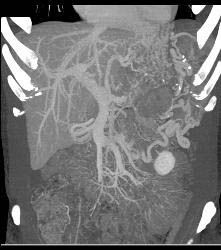

GIST Tumor With Ulceration